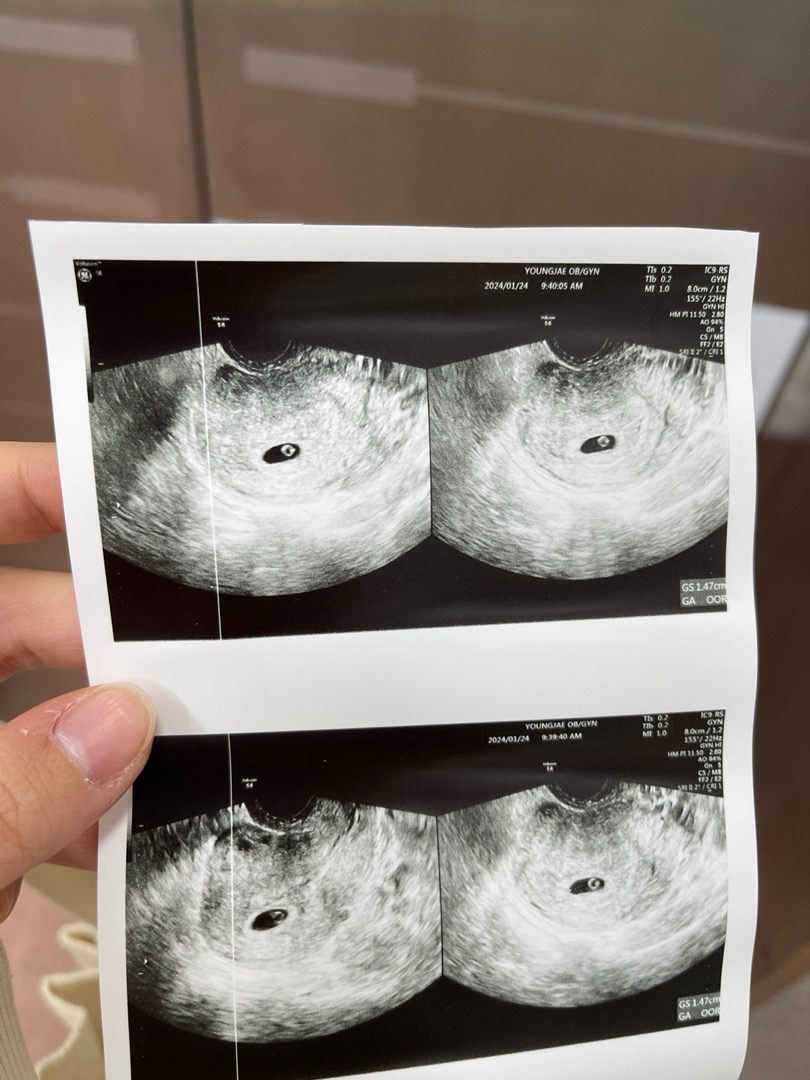

지난주 수요일에 난황보고왔어요